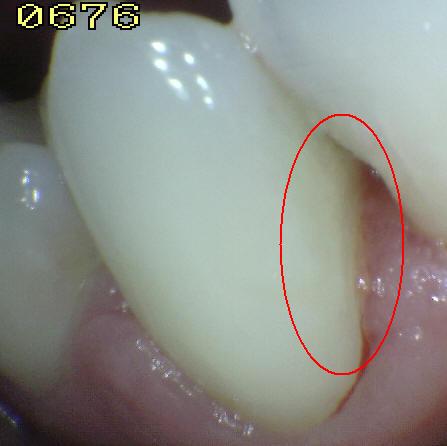

Código 4

(Caries Moderada): Sombra oscura

de dentina subyacente al esmalte intacto con o sin interrupción

localizada del esmalte

-

Esta lesión aparece como una sombra de decoloración

visible a través de una superficie de esmalte intacta, la que puede o no mostrar signos

de descomposición localizada del esmalte, como la microcavidad y /o discontinuida

< 0,5mm. después del secado con aire durante 5

segundos

La aparición de

la sombra se ve a menudo con más facilidad cuando

el diente está húmedo. El área oscura es una

sombra intrínseca que puede aparecer gris, negro-azul o

marrón-anaranjado,

a través de las paredes del esmalte vestibular, lingual o

palatino